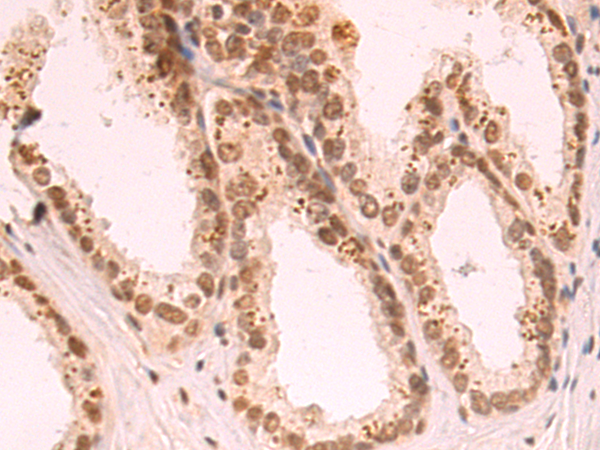

分类: 科研抗体货号: P12855别名: LRPDIT; LRP-DIT应用: IHC反应种属: Human, Mouse